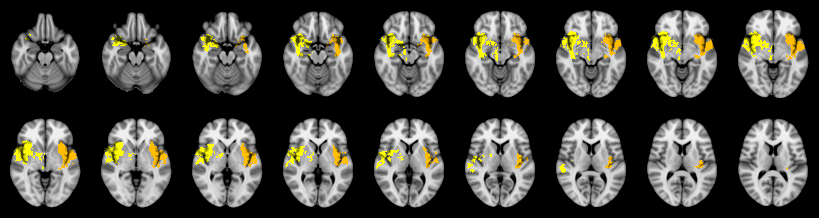

Pain study, Cluster extent, Corrected

Not combined

Combined

Mudholkar–George: